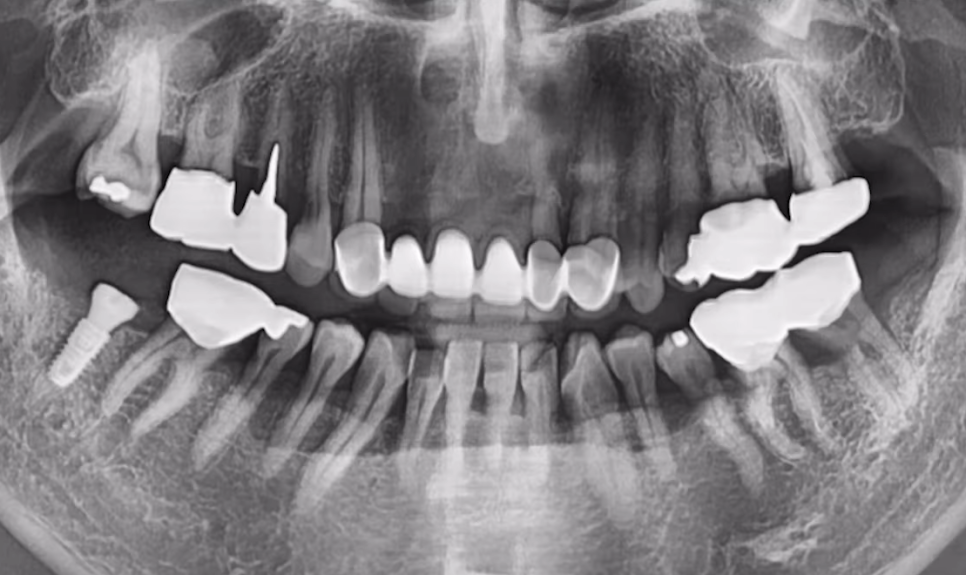

61세 남성 환자분이셨고

임플란트를 심기에는 전체적으로 염증이 많이 퍼져 있는 상태였습니다.

하여 발치를 결정한 치아들은 순차적으로 발치를 다 해드렸고,

염증 제거와 잇몸뼈 회복이 우선이었기에

뼈가 어느 정도 아물 때까지 3개월 정도 기다렸습니다.

그런데 사실상 남아 있는 뼈들도 부족한 상태고,

임플란트 심기에는 상악동 뼈도 굉장히 얇은 상태입니다.

이런 상태에서는 무리하게 식립하다가

임플란트가 상악동에 빠지는 사고가 발생할 수도 있습니다.

당일에 뼈이식과 상악동 뼈 이식을 해드려 뼈를 충분히 보강한 후, 동시 식립까지 진행했습니다.

상악동에 뼈 잘 이식된 것 보시이죠?

CT 사진으로 잘 식립된 것까지 체크해 드린 후 다음 날 반대편까지 안전하게 심어드렸습니다.